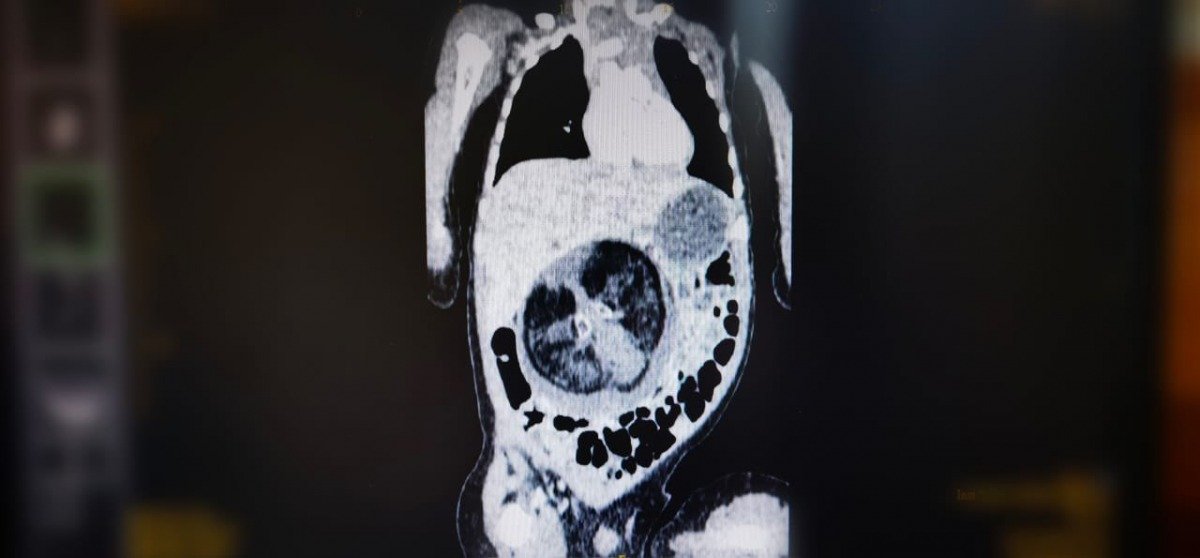

أفادت وكالة الأنباء العمانية، بأن قسم جراحة الأطفال بالمستشفى السلطاني في البلاد، أجرى عملية جراحية نادرة تمثلت في استئصال جنين من داخل جنين.

وأشارت الوكالة إلى أن العملية الجراحية التي جرت عبارة عن استئصال جنين من داخل جنين، لطفل يبلغ من العمر ثمانية أشهر.

كما نشرت صورا في “تويتر” أظهرت الصور الصوتية للجنين، وللحالة التي تمت معالجتها، وفريق طبي مختص.

يُذكر أن هذه الظاهرة الطبية تعرف ب” Fetus in feto” وتحدث بنسبة 1 من كل 500 ألف حالة ولادة حية على مستوى العالم.